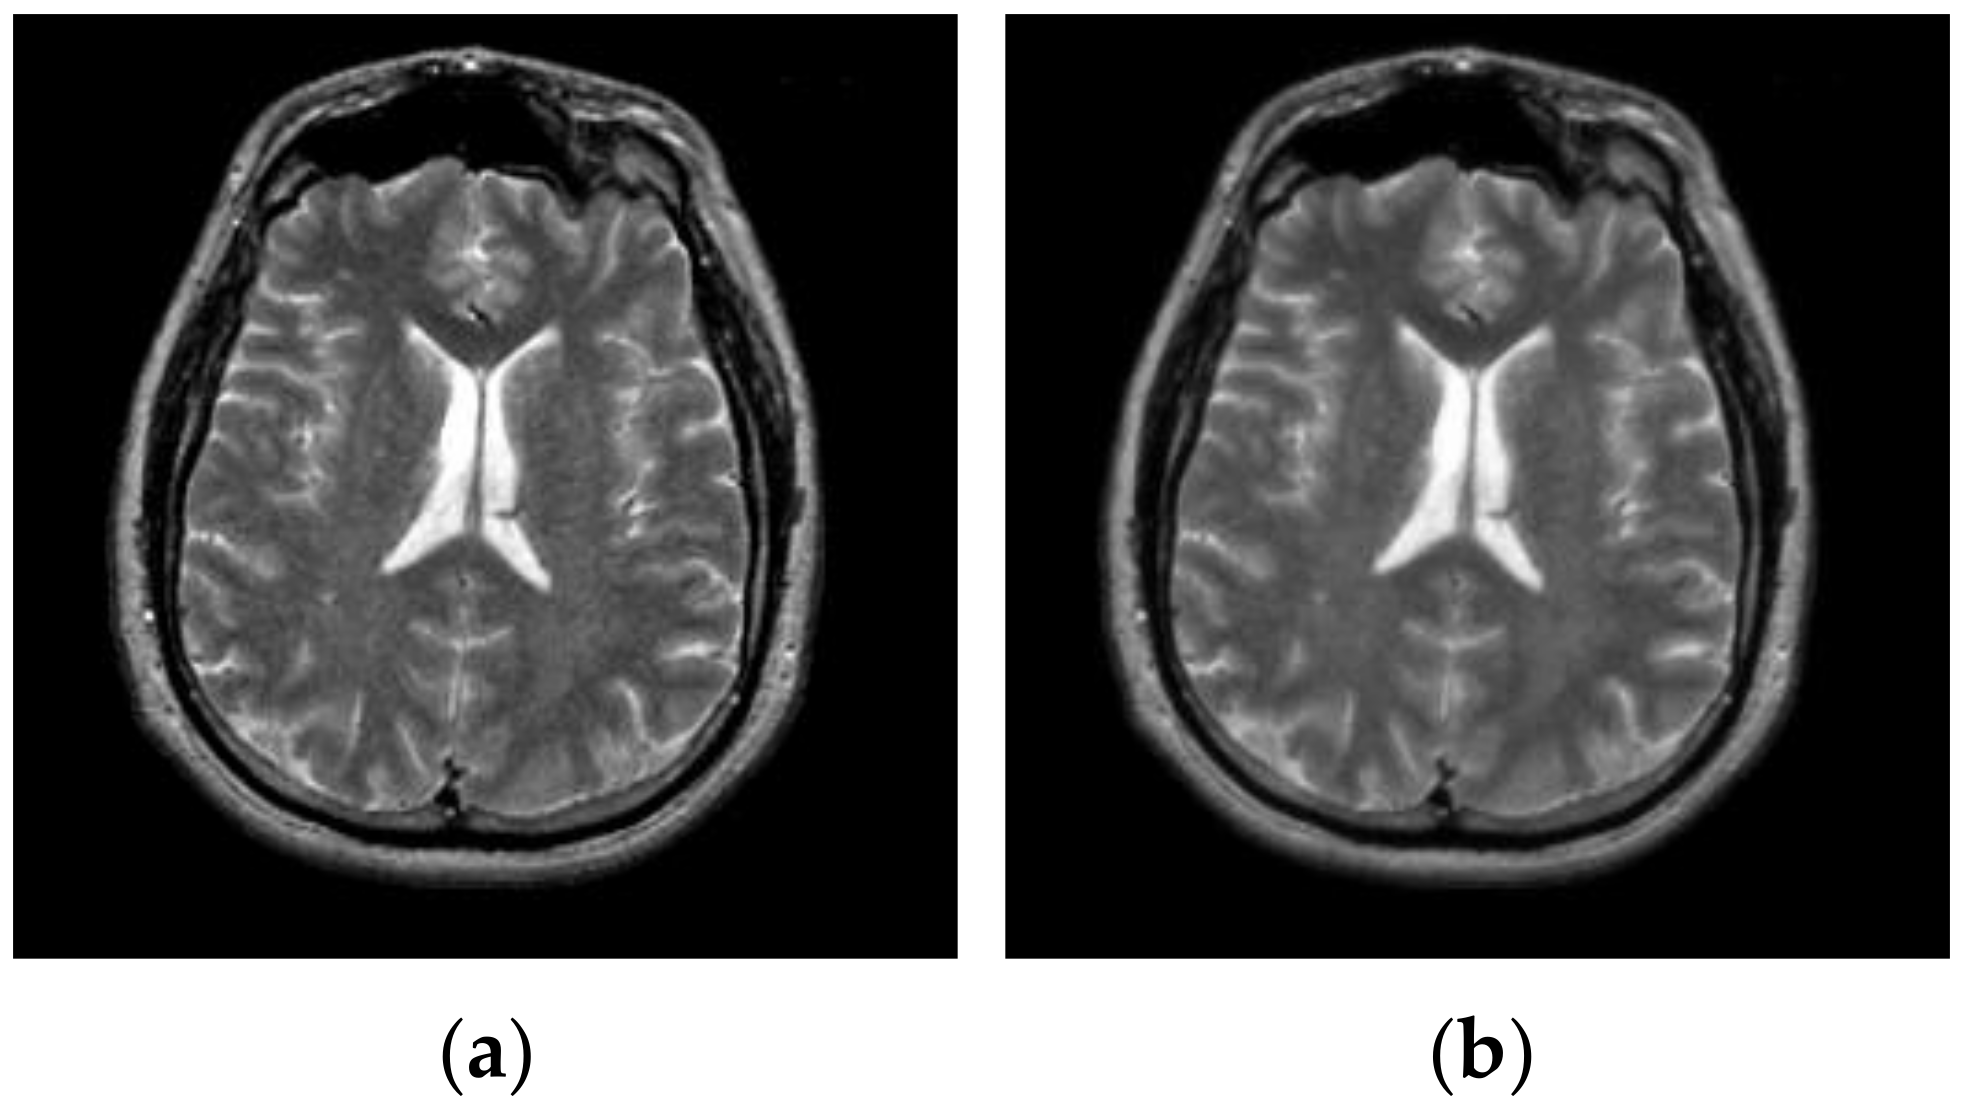

After hybrid L1 − L0 layer decomposition, the base layer of original image is used for segmentation in the framework of the proposed algorithm. Figure 7 displays an example of decomposition. In Figure 7, the first column contains two original images, and the second column contains two corresponding base layers. From Figure 7b, it can be seen that the base layers are visually smooth, and eliminate some weak edges.

Figure 7.

Original images and their corresponding base layers. (a) Original images, (b) base layers.